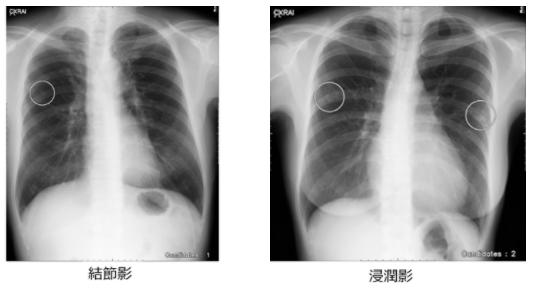

「CXR finding-i」は、専門医のスキルを学習したAIが胸部X線画像を解析し、医師による胸部X線画像の読影において、肺がんが疑われる所見である結節影や、肺炎や結核など感染症の所見である浸潤影の見落とし防止を支援します。特に、限られた時間の中で大量の診断をする必要のある健康診断においては、ワークフロー改善にも貢献できるものと考えています。

また、AI機能が病変候補の位置を表示する際には、読影の邪魔にならないシンプルな白い円形マークを採用しており、どの部分を何か所マーキングしているのかを明示します。病変の可能性のある箇所をピンポイントで表示するので、医師は瞬時にAIの表示箇所を見つけられるだけでなく、マークを消さずに示された部分の読影を行うことが可能です。